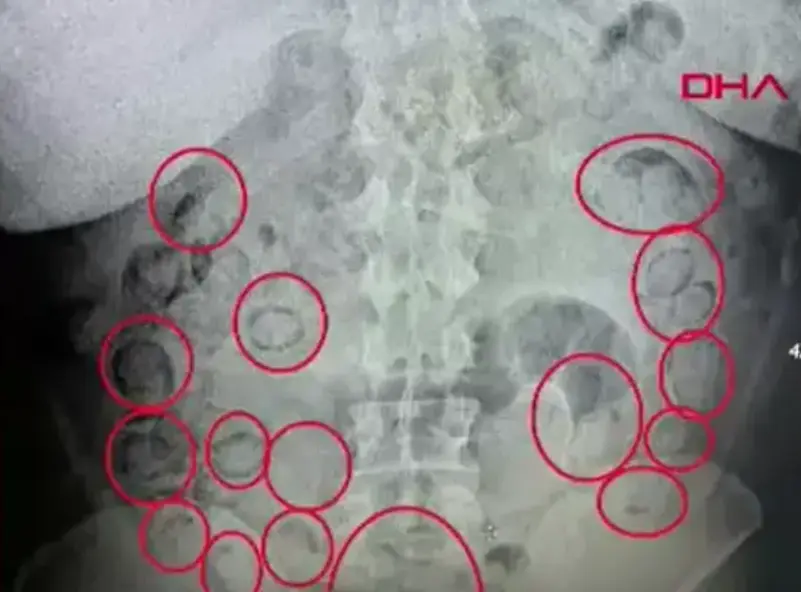

العثور على 433 جراماً من المخدرات في معدة رجل في اسطنبول

تمكنت الشرطة في مدينة إسطنبول، اليوم الجمعة، من إلقاء القبض بمحض الصدفة على رجلٍ كان “يخبئ” 433 غراماً من المخدرات…